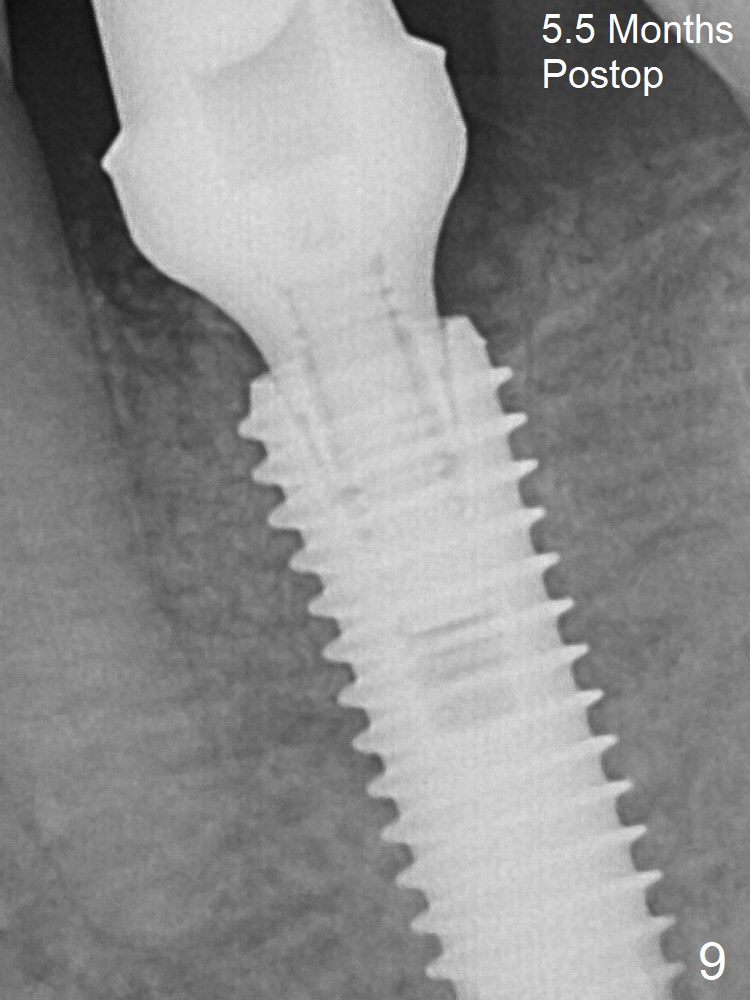

Due to severe buccal plate resorption, a shorter implant is placed (Fig.6; 5x15 mm in stead of 18 mm).  There is at least 2 mm gap buccally for Vanilla Graft, which is also placed next to the implant and the neighboring root (Fig.7 double * ).  Abutment: 6.5x4(4) mm.  The distal (D) socket is packed with Collagen Plug before bone graft coronally (single *).  Both the mesial and distal sockets heal 5.5 months postop (Fig.9), although the apical portion of the distal socket was not filled with allograft (Fig.7 D).  The implant was placed mesial.  The abutment may be changed to 5.5x5(3) mm or 4.5x15 degrees 3 mm cuff before impression.  Next case, osteotomy should be established in the middle of the socket by using Lindamann bur amply.